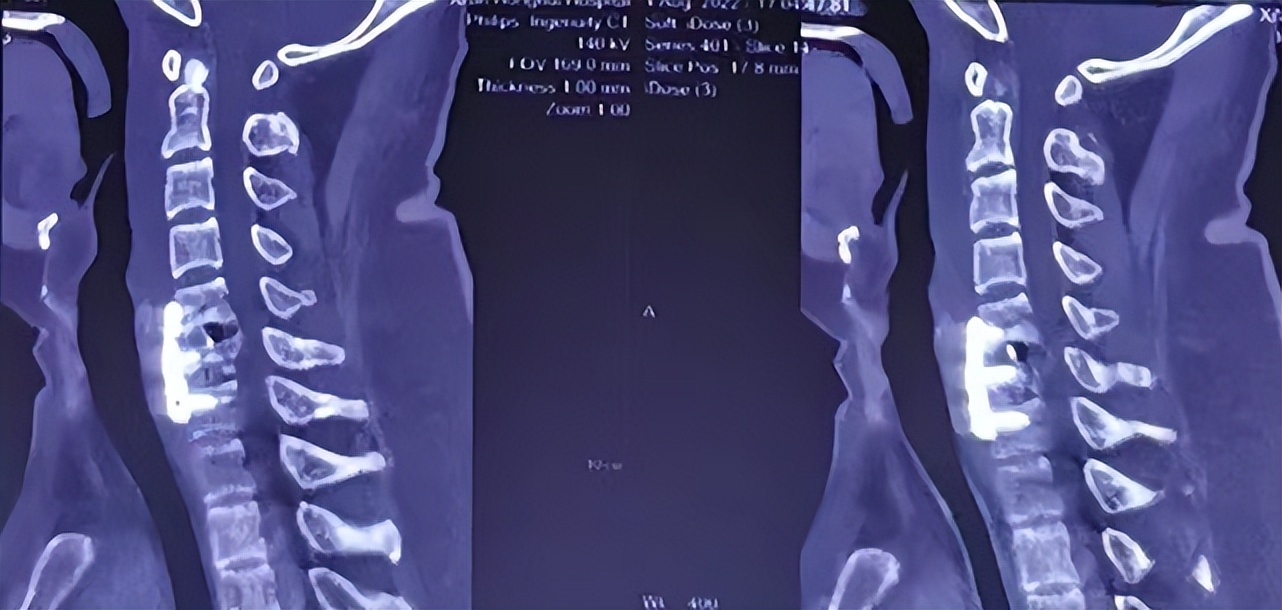

术后脊髓损伤平面

术后,结合ERAS现状及脊髓损伤救治标准,急诊EICU唐海峰主治医师及其团队精细化的围术期管理:24小时的标准的大剂量激素冲击+雾化排痰+床上的肺功能锻炼+被动及主动下肢,积极的抗炎和早期肠内营养的供给。未出现呼吸衰竭、下肢静脉血栓及压疮等并发症,术后4天转入康复科进行康复治疗。在多方面的努力下,大小便功能逐步恢复,伤后4周复查,患者可下地行走,双上肢肌力3级,双下肢肌力达到4级+,痛温觉、触觉逐渐恢复。 伤后5周随访,患者双上肢前臂尺侧和尺侧三指麻木、疼痛,双下肢麻木。双上肢肌力三级+,双下肢肌力5级-,行走已经完全不是问题,且大小便恢复正常,治疗效果良好。